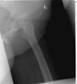

Post

Op

Xrays